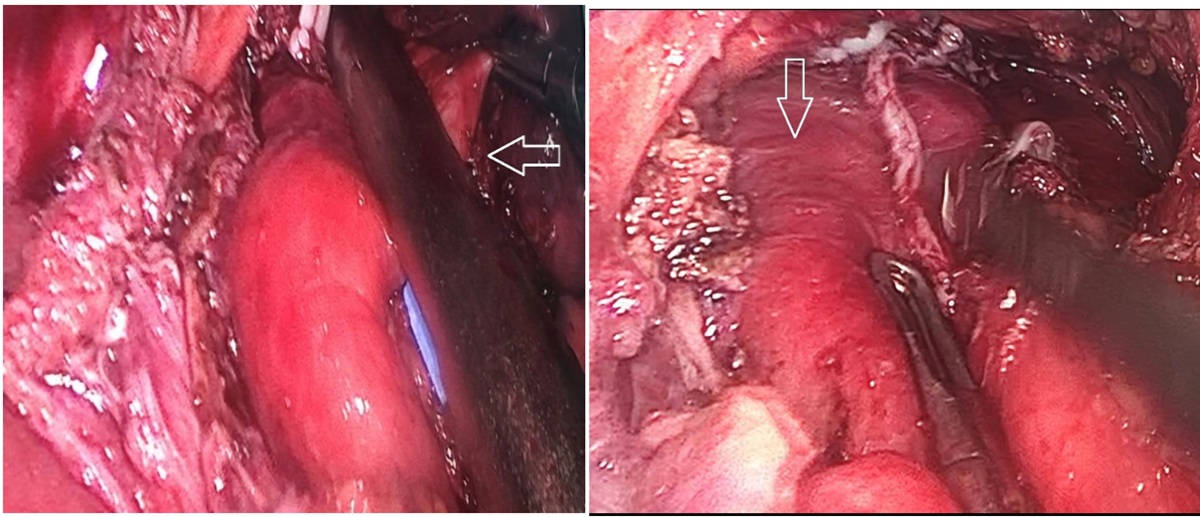

1. Trường hợp thứ nhất: Bệnh nhân nam, 48 tuổi vào Bệnh viện Trường Đại học Y Dược Cần Thơ vì khó nuốt, cách nhập viện khoảng 1 năm, bệnh nhân cảm thấy khó nuốt với thức ăn đặc, cảm giác khó chịu sau xương ức, thỉnh thoảng có ợ nóng và nôn ra thức ăn. Cách nhập viện # 3 tháng, bệnh nhân cảm giác nuốt nghẹn với thức ăn lỏng, nước, cảm giác khó tiêu, ợ hơi nhiều sau ăn, đôi khi có ho khan, sụt cân # 2-3 kg/năm. Không có yếu tố tăng nặng hoặc giảm nhẹ cụ thể, khám sức khỏe không phát hiện bất thường. Chỉ số BMI của bệnh nhân trong giới hạn bình thường. Khi khám, thấy bụng mềm nhưng có cảm giác đau vừa phải ở thượng vị. Điện tâm đồ, siêu âm tim và chụp X-quang phổi của bệnh nhân đều bình thường. Vì vậy, các nguyên nhân tim và phổi đã được loại trừ. Các xét nghiệm của bệnh nhân bao gồm xét nghiệm máu thường quy, sinh hóa và siêu âm ổ bụng chưa ghi nhận bất thường. X-quang thực quản-dạ dày có uống thuốc cản quang: túi thừa thực quản 1/3 dưới. MSCT ngực: Túi thừa thực quản 1/3 dưới, tổn thương mô kẽ và xơ đỉnh phổi (P) nghĩ tổn thương cũ

Hình 1: Túi thừa thực quản 1/3 dưới thực quản trên X-quang thực quản – dạ dày có cản quang, và trên MSCT ngực (mũi tên trắng)